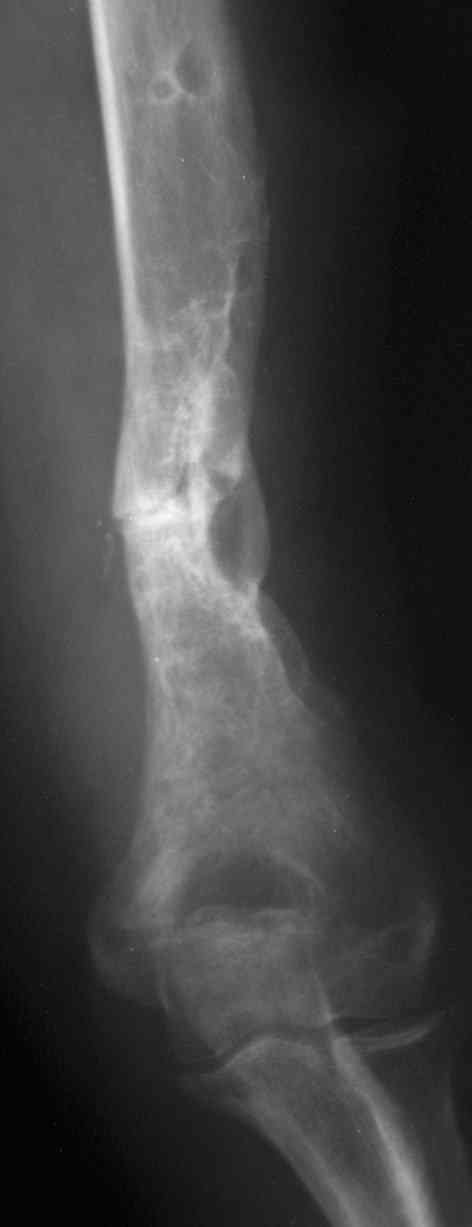

На примере два случая, извиняюсь за качество снимков, снимки и случаи из бывшего союза.

Первая больная с "успехом" была прооперирована 6 раз различными методами открытого и закрытого

остеосинтеза, включая то, что в Кисловодске заезжим австралийским "кудесником" на ложный сустав уложена скорлупа от страусиновых яиц. Последняя операция одиноким локинг плейт в одной из клиник.

Через год по поводу тех же проблем сделали ревизию, оригинальную пластину оставили как есть, только укрепили добавлением еще одной пластины и сделали костную пластику.

Через два месяца увидели признаки консолидации.

Второй случай, также после множественных операций:

пластина, аппарат, серкляж и парез нерва.

Также ревизия, из-за низкого состояния доступ был

сделан через остеотомию локтевого отростка.

Ложный сустав фиксирован двумя локинг плейт с

аутокостной пластикой, также через два месяца увидели признаки консолидации.

Движение в суставе разрешили в две недели.